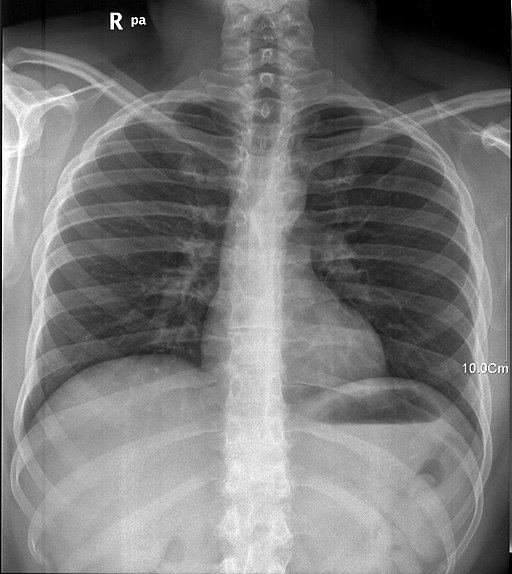

无症状肋骨骨折诊断中的X光片。需注意骨骼结构没有任何损伤。

Dockery:你得了一种非常罕见的癌症。无症状肺癌,具体而言。它和常见类型的癌症一样危险,但缺少了很多典型症状。很幸运我们发现了。

Dockery:让我说明下。我发现你来我这面诊的时候咳嗽不带血,我就开始怀疑了。这就是无症状肺癌的典型征兆。在有症状肺癌里,你会咳血、喘鸣、喘不过气。与之相反,无症状变体就很难发现。如这个名字所示,它只能通过缺乏症状来诊断。我对此领域很有经验,我此前受过肿瘤医师的培训—换个医生可能就发现不了你病的这么重。